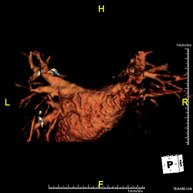

- Intracranial MRI angiography

This non-invasive diagnostic procedure uses an electromagnetic field and radio waves (from a transmitter and receiver) to acquire high-definition anatomical images of the cerebral arteries. It is a radiation-free procedure. In most cases, paramagnetic contrast (gadolinium) is required. It enables non-invasive angiographic studies using a gadolinium injection, with subsequent 2D and 3D reconstruction using specialised workstations. Indicated for: vascular malformations, cerebral artery aneurysms, arteriosclerosis.